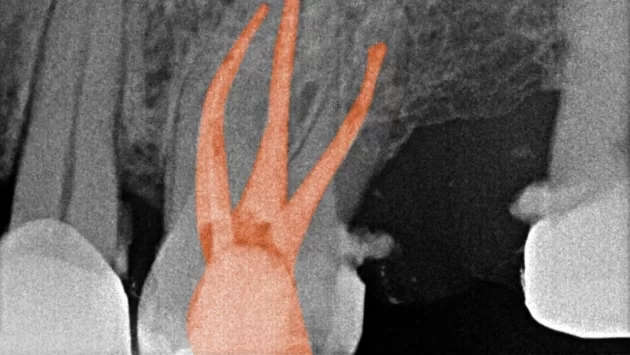

3D CBCT for Teeth Scanning:

Providing detailed 3D images of the teeth and surrounding structures. This aids in diagnosing complex root canal cases by offering a comprehensive view, enabling precise treatment planning.